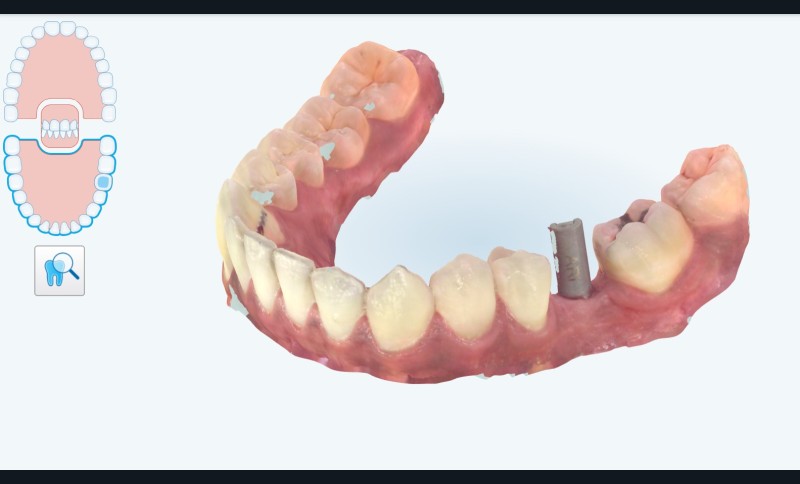

3 mois après cicatrisation , nous reprenons notre camera en main, et cette fois ci, nous allons prendre l’empreinte de notre « scanbody » qui est le transfert d’empreinte numérique (fig. 4) correspondant à notre implant (Megagen). C’est la que la magie opère… Fini les portes empreintes individuels, à perforer etc. On place le scanbody et on prends l’empreinte (haut , bas , occlusion). On peut même prendre le profil d’émergence sur un scan supplémentaire en quelques secondes.

L’empreinte est envoyée sur la plateforme et la conception est réalisée (fig. 5). Idem à ce stade vous pourrez valider la forme, le profil d’émergence etc.